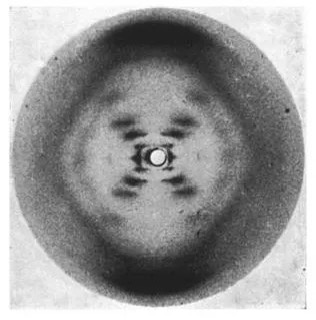

보통 우리는 DNA 이중 나선을 발견한 과학자로 제임스 왓슨과 프랜시스 크릭을 떠올립니다. 그들은 1953년, 이중 나선 구조를 설명하는 논문을 발표하면서 전 세계 과학계를 놀라게 했습니다. 하지만 그 배경에는 로잘린드 프랭클린이라는 뛰어난 과학자의 공로가 크게 자리 잡고 있었습니다. 프랭클린 박사는 엑스선 회절 기술을 사용하여 DNA 구조를 실험적으로 증명하는 데 성공하였고, 그녀의 연구는 왓슨과 크릭이 이론적 틀을 완성하는 데 결정적인 영향을 미쳤습니다.

그녀가 남긴 엑스선 이미지를 보세요. 별빛처럼 퍼지는 그 이미지는 그녀가 과학계에 남긴 불멸의 흔적입니다. 우리는 그 빛을 이어받아 더 넓은 세계를 밝힐 책임을 가지고 있습니다. 지금도 불철주야 실험실에서 고생하고 계신 연구자 여러분도 질문을 멈추지 않고, 다음의 ‘이중 나선’을 향해 도전해 보시기 바랍니다.